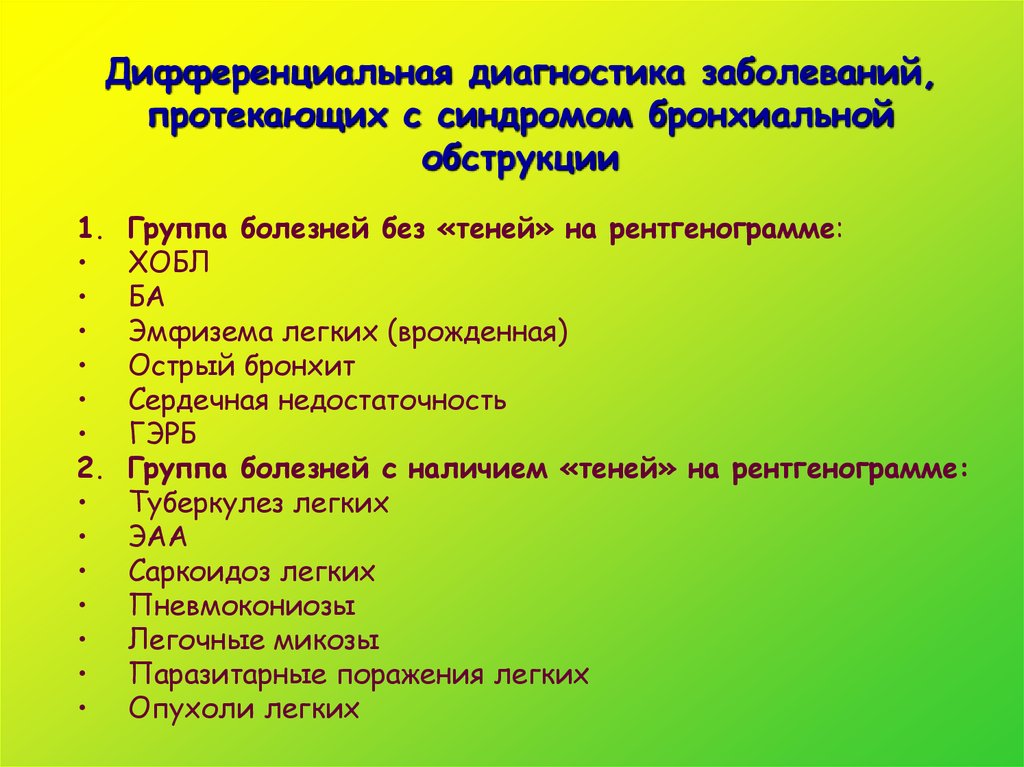

Дифференциальная диагностика заболеваний плевры